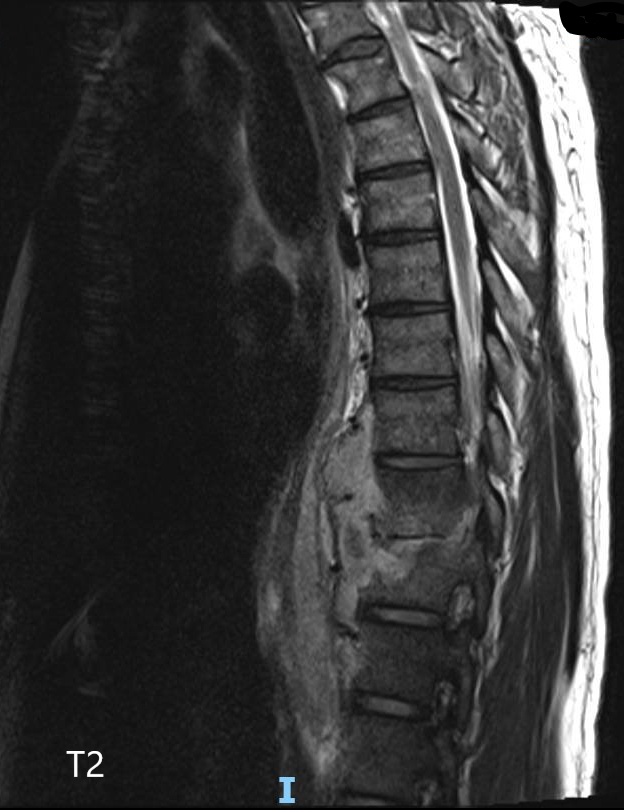

Vous voyez en consultation M. M., 52 ans, pour des douleurs dorsales évoluant depuis quelques semaines. Il est d’origine mauritanienne, travaille dans le bâtiment, et n’a pas d’antécédent particulier, ni de consommation de tabac ou d’alcool. Il ne prend aucun traitement.

Il vient vous voir car il ne peut plus travailler du fait des douleurs qui sont devenues permanentes, y compris la nuit, sans irradiation. Il n’a pas pris sa température mais signale des sueurs nocturnes depuis dix jours. Il a également constaté une faiblesse des membres inférieurs lorsqu’il marche longtemps, l’obligeant à s’arrêter, sans douleur. Il n’a pas de trouble sphinctérien à l’interrogatoire.

Il faut donc évoquer une pathologie rachidienne inflammatoire/infectieuse/tumorale avec syndrome de compression médullaire partiel se traduisant uniquement par une claudication médullaire : celle-ci correspond à un syndrome pyramidal, démasqué par l’effort.